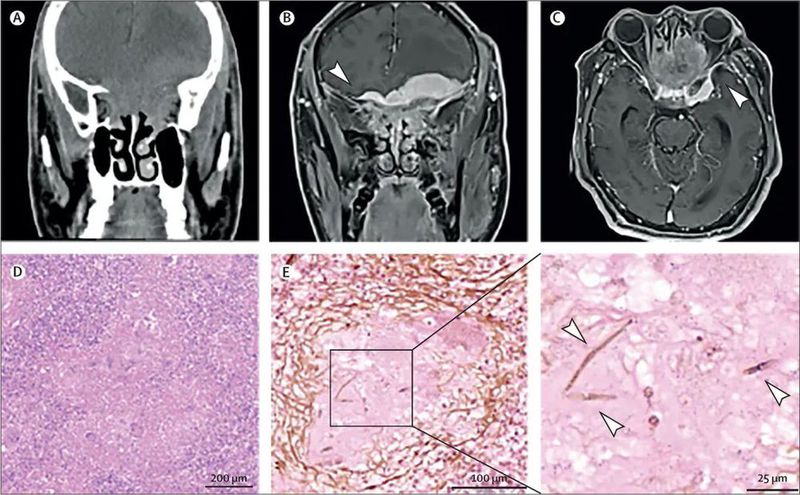

患者初步疑诊为脑膜瘤,并接受了病损部分切除术。术后病理结果为肉芽肿性炎,未见肿瘤征象(图D)。Grocott六胺银染色发现稀疏的真菌菌丝(图E),经宏基因组二代测序确诊为黄曲霉(Aspergillus flavus)感染。患者最终确诊为慢性肉芽肿性侵袭性真菌性鼻窦炎。

(D) 苏木精-伊红染色(×10)显示肉芽肿性炎症。

(E) Grocott六胺银染色图像,×20(左)和×60(右)显示稀疏的真菌菌丝(箭头所示)。